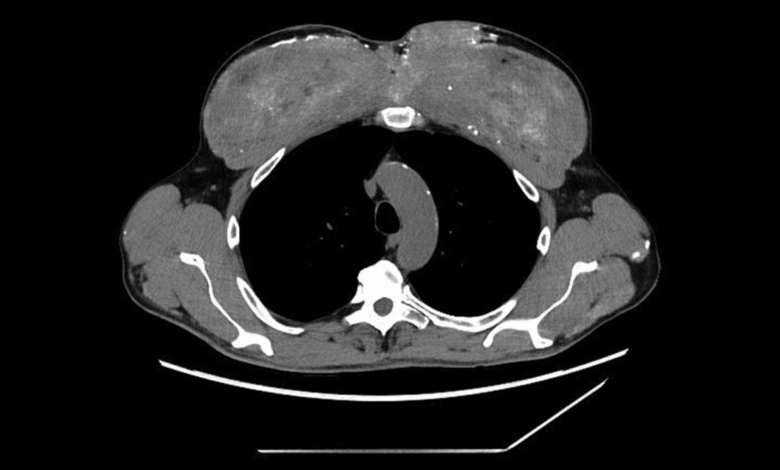

قرر الفريق الطبي إجراء فحوصات تصوير مقطعي، ليتضح أن التكلّسات لا تقتصر على الدم فقط؛ فقد كانت منتشرة في الكليتين والبنكرياس والمعدة، كما ظهرت بقع تشبه الندبات في الرئتين. غير أن أكثر ما أثار الريبة كان التغيّر الغريب في عضلات الصدر، التي بدت متكلّسة بشكل كثيف وغير طبيعي.

تم إدخال الرجل للعلاج، فحصل على مدرّات البول، والسوائل الوريدية، والستيرويدات، وأدوية لخفض الكالسيوم. انخفضت مستويات الكالسيوم مؤقتاً، لكنه وبعد أسابيع قليلة عاد إلى المستشفى بمشكلة أكبر وهي أن الكالسيوم يرتفع من جديد دون أي سبب واضح. عند إعادة الفحص، لُوحظ أن عضلات الذراعين والصدر مشوهة وغير طبيعية، تماماً مثلما ظهر في صور الأشعة.